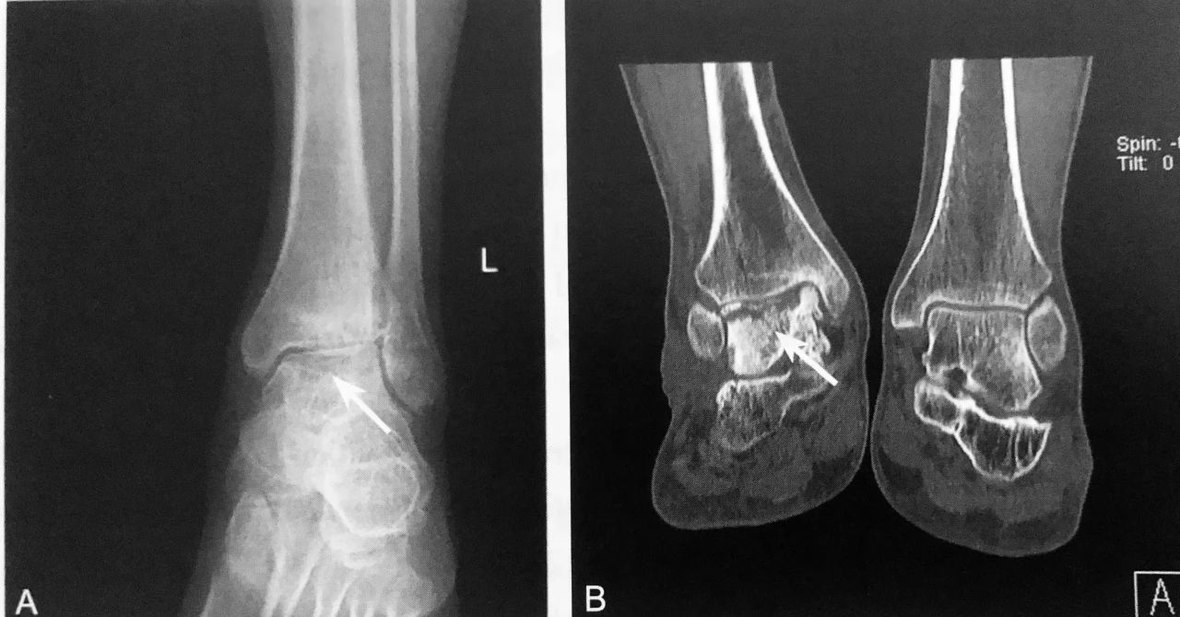

霍 金 斯 征

A.左踝关节 ⅹ 线正位片示距骨圆顶皮质下见一横行线样透亮带(箭头),霍金斯征阳性;B.不同患者,右踝关节 CT 冠状位重建示距骨圆顶皮质下细线样低密度带(箭头),霍金斯征阳性

判读要点:

1、霍金斯征在骨折后(尤其是距骨颈垂直骨折)对距骨 AVN 的防治诊断中具有基础性筛选作用;

2、距骨颈垂直骨折后(6±8)周在踝关节正位片或 CT 冠状位重建上观察;

3、表现为距骨圆顶软骨下横行线样透亮带具有较高的敏感性,但特异性较低;

4、阳性表明骨折后距骨主动性充血后维持血液供应,不大可能发生缺血性坏死。阴性高度提示距骨有缺血性坏死的危险;

5、霍金斯征的有无可以作为是否行 MRI 或 CT 评估距骨缺血性坏死与帮助指导适当治疗的指标。